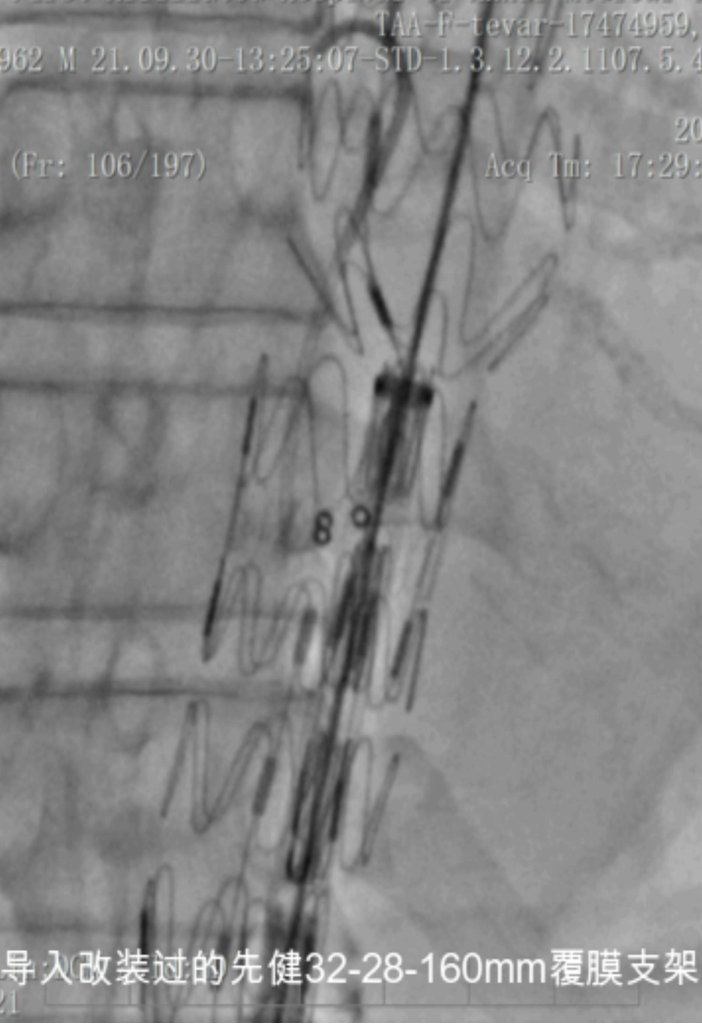

开窗病例

病例1 两开窗:

病例2 四开窗:

手术时间382分钟

造影剂用量320ml